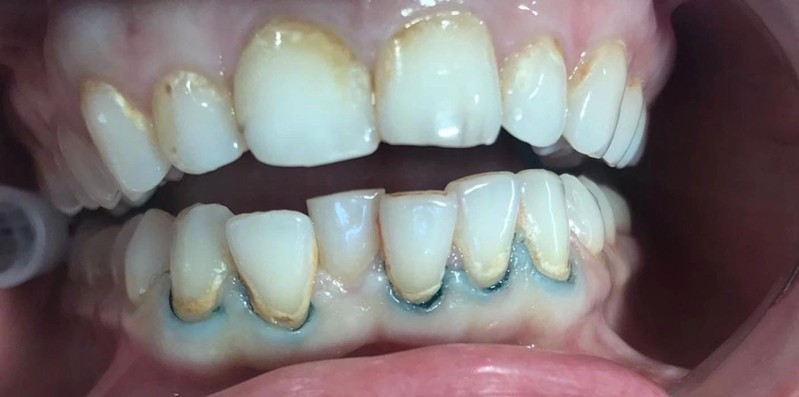

Стоматологическая клиника ЧАСТНАЯ ПРАКТИКА

Чистка зубов Air-flow

Чистка зубов ультразвуком с полировкой. Доктор очень бережно отнесся к сгустку крови образовавшемуся на травмированном камнем участке десны. Это даст возможность максимально быстро восстановиться сосочку десны. Наложенная в дальнейшем лекарственная повязка ускорит процесс.

Доктор: Фалилеев Алексей Константинович